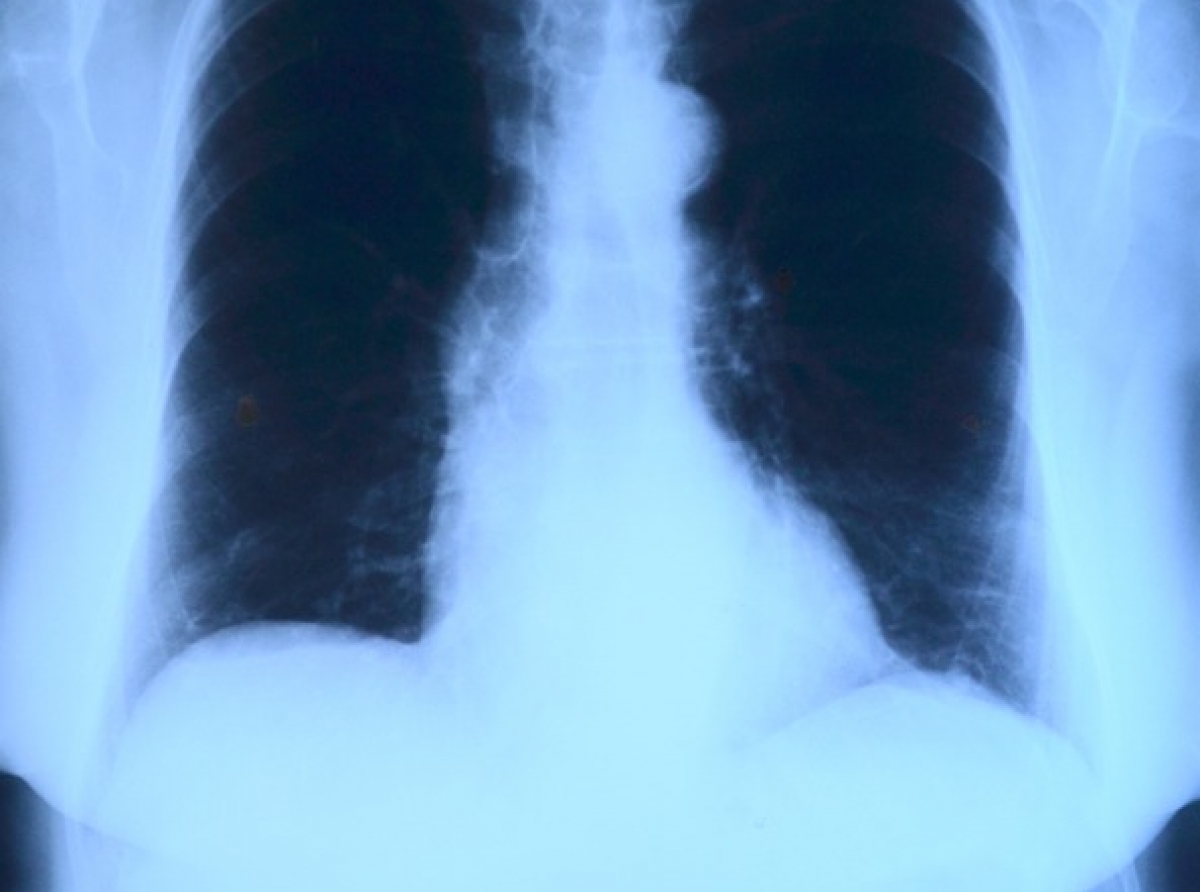

Своевременное выявление и профилактика туберкулеза – одно из направлений работы Артемовской ЦРБ. В учреждении организованы и проводятся в массовом (по эпидемическим показаниям), групповом (по эпидемиоло-гическим показаниям) и индивидуальном порядке рентгенофлюорографические осмотры населения.

Имеется два стационарных цифровых аппарата для исследований органов грудной клетки – один в п.Буланаш, второй - в г. Артемовский (акушерско-гинекологический корпус).

В 2021 году по утвержденному плану в АГО нужно обследовать 38122 человека. За 10 месяцев уже осмотрено 31410 человек (82,4 % от годового плана или 94% от плана 10 месяцев, на КТ обследовано из числа осмотренных 6388 человек, это 20% от общего числа осмотренных).

В ходе осмотров медики выявили 14 случаев активного туберкулеза легких, 24 случая рака легких и 76 прочих заболеваний.